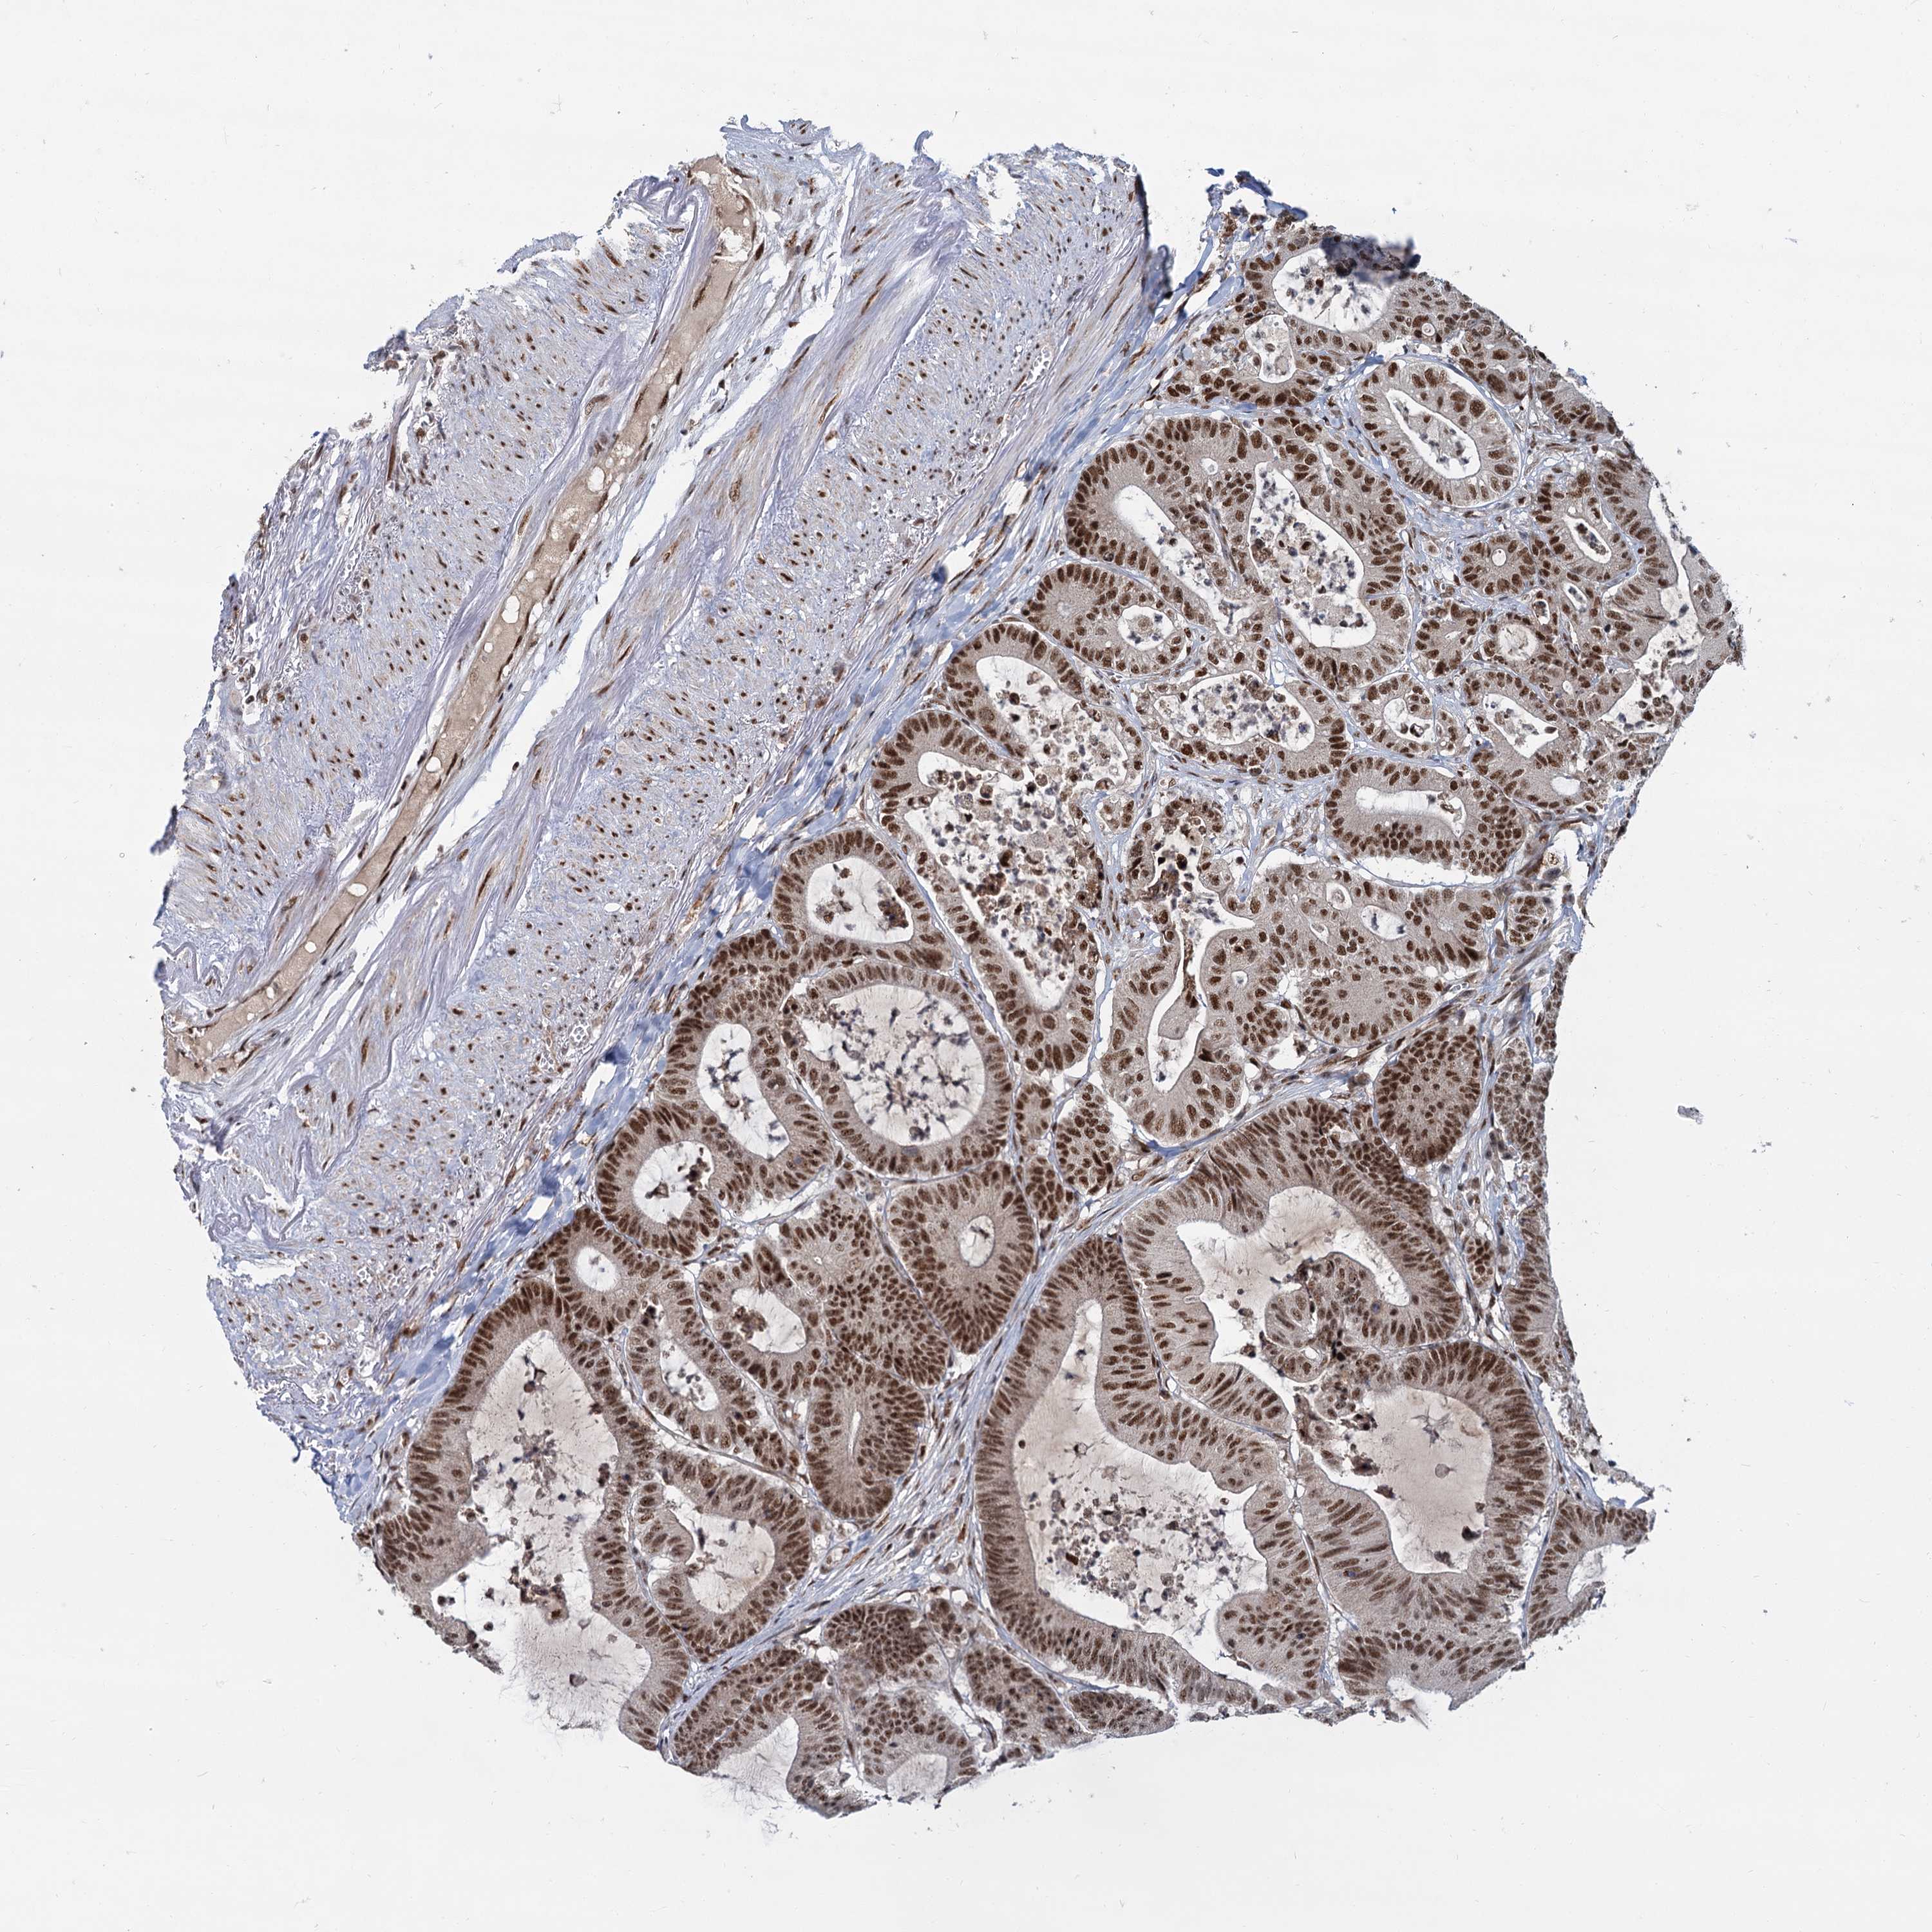

CANCER COLORECTAL CANCER Show tissue menu

Colorectal cancer

Human cancer

Rectum adenocarcinoma